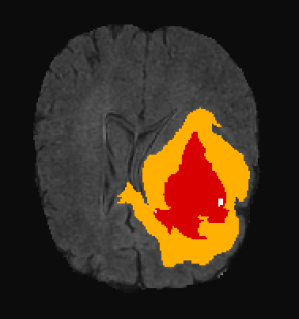

3.3 Visual analysis

Figure 5 shows two subjects among the quantitatively better (first row) and poorer (second row) results. In both cases, it can be visually appreciated that our method correctly segments the whole tumor region. For the subject shown in Figure 5.a, the system is able to properly capture all tumor regions, meaning that the first network is able to correctly localize the tumor and the second network is able to capture differences between tumor regions. On the other hand, in Figure 5.b, we show a case where even though the tumor is correctly localized by the first network, the second isn’t able to properly detect different tumor subregions. We see that edema (ED - label 2) is overrepresented in our segmentation in detriment of smaller classes: GD-enhancing tumor (ET - label 4) and the necrotic and non-enhancing tumor (NCR/NET - label 1). This effect can also be inferred from lower values in ET and TC dice coefficients.